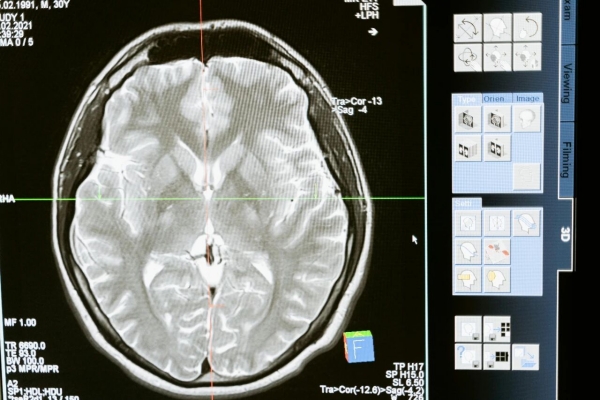

头颅增强MRI检查

这是脑转移诊断首选的影像学检查方法,其具有无辐射、软组织分辨率高、灵敏度高等优点。存在MRI禁忌症的患者,则可以选择头颅增强CT检查。